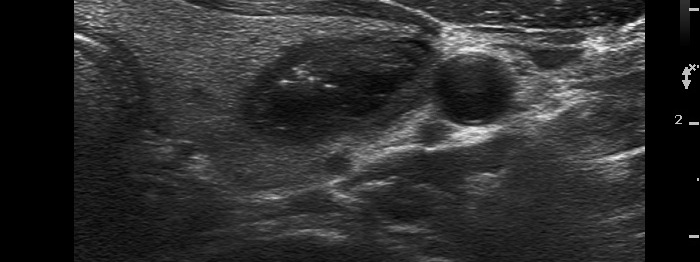

Follicular adenoma (histological diagnosis)

Before aspiration of 2 mL cystic fluid |

There are numerous hyperechogenic granules in the lower pole of the nodule. These figures might be confused with punctate echogenic foci (microcalcifications), as happened in this case. However, several have dorsal tail and therefore the remaining without a tail likely belong also to the same subgroup.